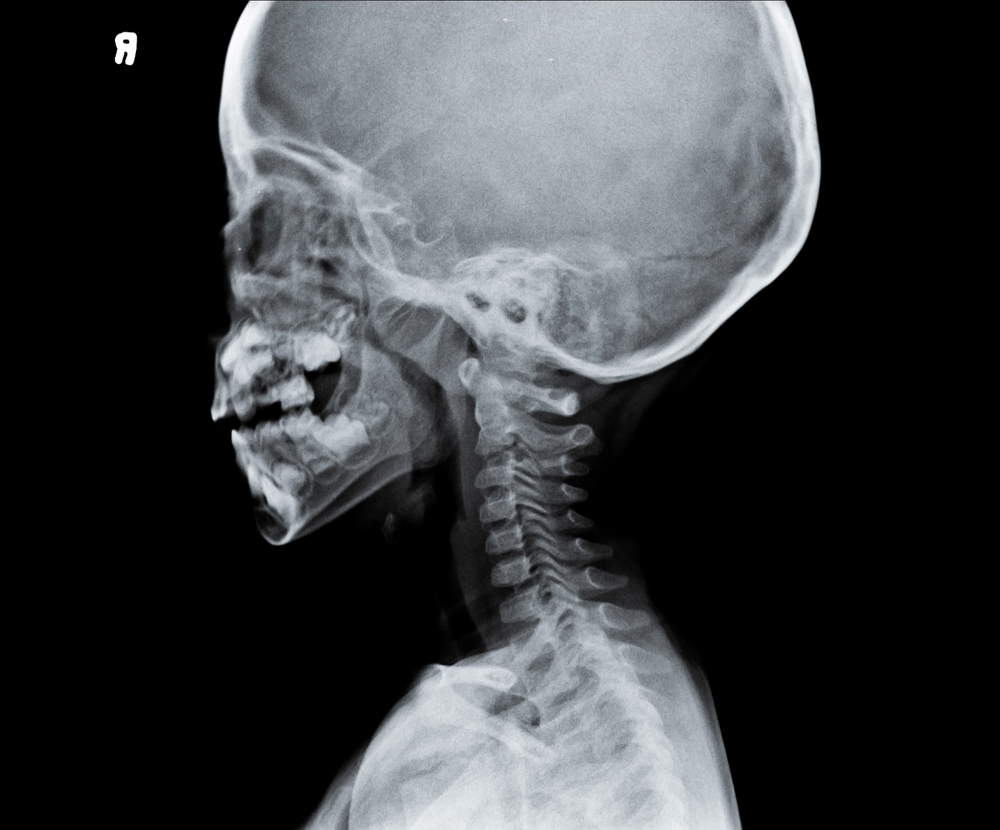

- рентгенографию шейного отдела позвоночника;

- компьютерную или магнитно-резонансную томографию шейного отдела позвоночника.